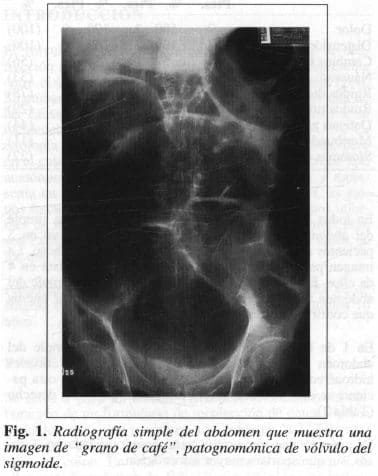

En todos los pacientes se practicó una radiografía simple del abdomen. El diagnóstico de VS fue conclusivo en 5 pacientes (71 %); en los otros 2 fue apenas sospechoso. La imagen patognomónica de “grano de café” fue vista en 4 de ellos. En I de los casos en que la radiografía simple del abdomen fue sospechosa, se practicó un colon por enema que confirmó el diagnóstico.

El estudio radiológico de mayor utilidad es la radiografía simple del abdomen. El hallazgo característico del VS, especialmente en la proyección vertical, es la llamada imagen en “grano de café”, que consiste en 3 líneas densas, curvas, que convergen en el sitio de la estenosis, y terminan en una masa igualmente densa que corresponde a la torsión de la raíz del mesenterio.

Las paredes mediales adyacentes forman la línea central densa. Las líneas externas, una a cada lado de la central, corresponden a las paredes de las asas adyacentes del colon ascendente a la derecha, y del colon descendente a la izquierda (Fig. 1). Cuando la válvula ileocecal es incompetente, el gas del colon pasa hacia el íleon terminal y se pueden observar niveles de líquido y gas en escasa cantidad. La porción del colon distal a la torsión, usualmente está colapsada y hay ausencia de gas en ella (24, 25).